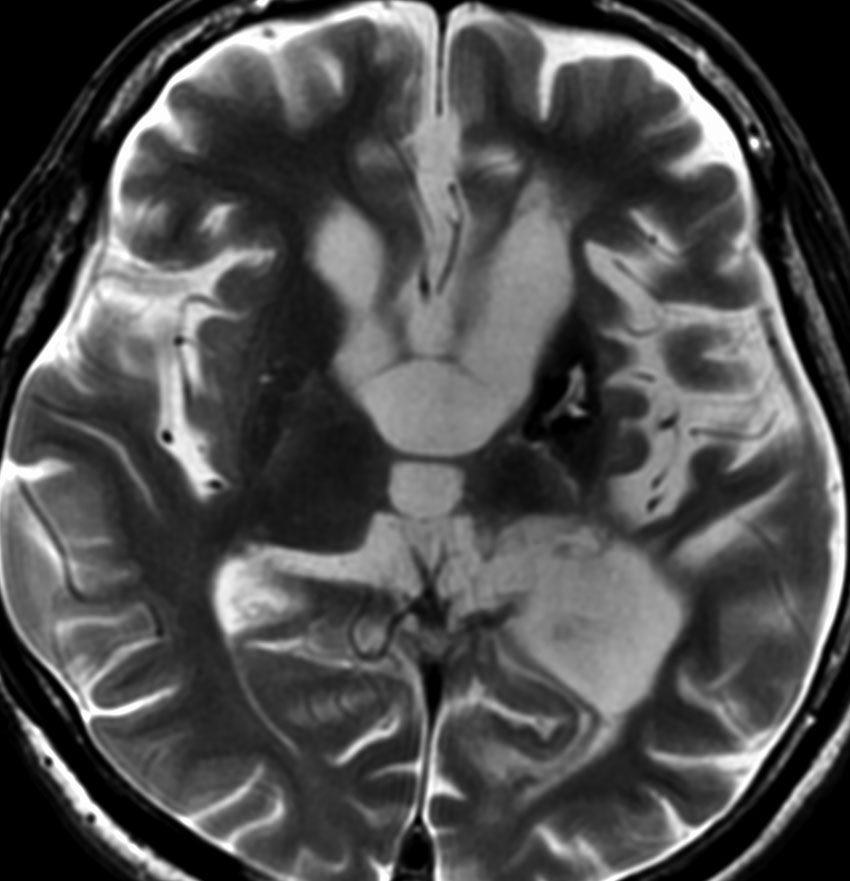

germinomaの視床浸潤:ミッキーマウスの耳

松果体ジャーミノーマは両側視床に浸潤して視床浮腫を生じます。真ん中に第3脳室後半部の割れ目が残っているのが特徴的な所見です。ミッキーマウスの耳みたいになります。かなり特異的な所見であり診断に有用です。右下は治療後です。